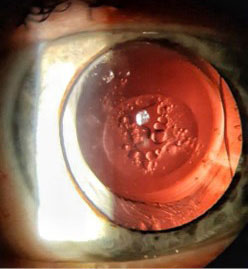

In both eyes: anterior chambers — deep, pupils were round, the IOLs were centered in the capsule bag, the posterior capsulorhexis were round. The right eye: the optical zone was transparent, the left eye: lens epithelial cells were in the optical zone on the posterior surface of the IOL (fig. 1, 2). The fundus of the eye was examined after the instillation of mydriatic. The optic nerve head is pale pink, with clear boundaries. Excavation of the optic nerve disc is widened, deep. According to OCT data the retinal nerve fiber layer (RNFL) and the ganglion cell complex were within normal limits, the macular region was normal.

Fig. 2. Patient's left eye, posterior capsulorhexis, rounded. Elschnig cells on the back of the IOL

Diagnosis: “Pseudophakia in both eyes. Secondary cataract (visual axis opacification) of the left eye”.